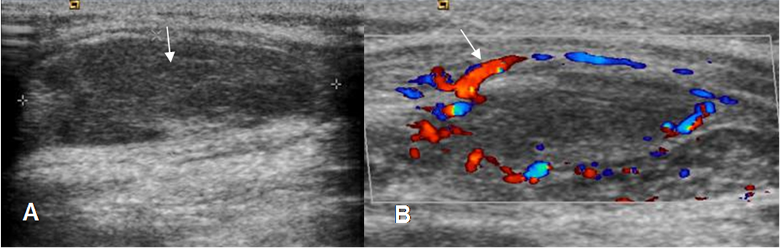

Fig 35. Absceso de tejidos blandos.

A: Ecografía. Imagen ovalada e hipoecoica, de bordes parcialmente definidos.

B Ecografía.doppler. La lesión presenta incremento en la vascularización de sus bordes, correspondiendo a incipiente formación de absceso.